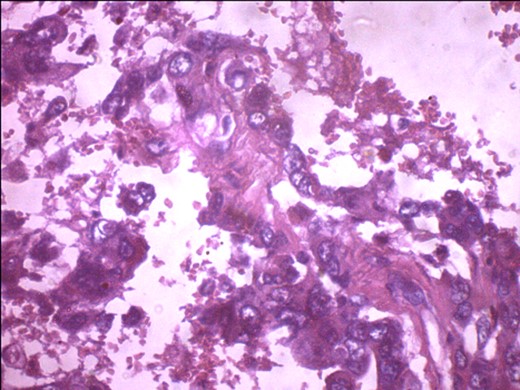

A 57-year-old woman presented with 5/12 history of left breast lump which gradually increase in size and became painful. Menarche was at 13 years without oral contraception. She had four confinements, the first being 20 years. Each child was breastfed for 8 months. No family history of breast cancer. Clinical examination showed breast asymmetry. Left breast was oedematous, shiny with extensive peau d'orange. Patient applied herbal preparations with multiple superficial skin excoriations. Outer quadrant breast mass was 8 cm, hard, with attachment to skin and underlying structures. No palpable axillary lymph node was felt and axillary ultrasonography, though desirable, was not done. Liver was not enlarged. Chest X-ray and abdominal ultrasound scan showed no involvement. Initial breast biopsy revealed an infiltrating atypical spindled tumour with hyperchromatic nuclei, which was both S100 and tyrosinase-positive. Tumour fungated with a darkly pigmented surface despite two cycles of neoadjuvant doxorubicin-based chemotherapy. Left simple mastectomy (Fig. 1) and axillary sampling (Fig. 2) of the sentinel and another slightly enlarged node were done, revealed a triple-negative invasive ductal carcinoma (Figs 3–6), with melanocytic differentiation (Figs 7 and 8), positivity for S-100 and patchy positivity for tyrosinase, an enzyme involved in melanin formation from dihydroxyl phenyl alanine. Only the sentinel node was involved, with the other showing reactive changes. Core biopsy of the tumour had ductal elements and was triple-negative.

S-100 cytoplasmic positivity in keeping with melanocytic differentiation. Immunohistochemistry.

Tyrosinase positivity in keeping with melanocytic differentiation.